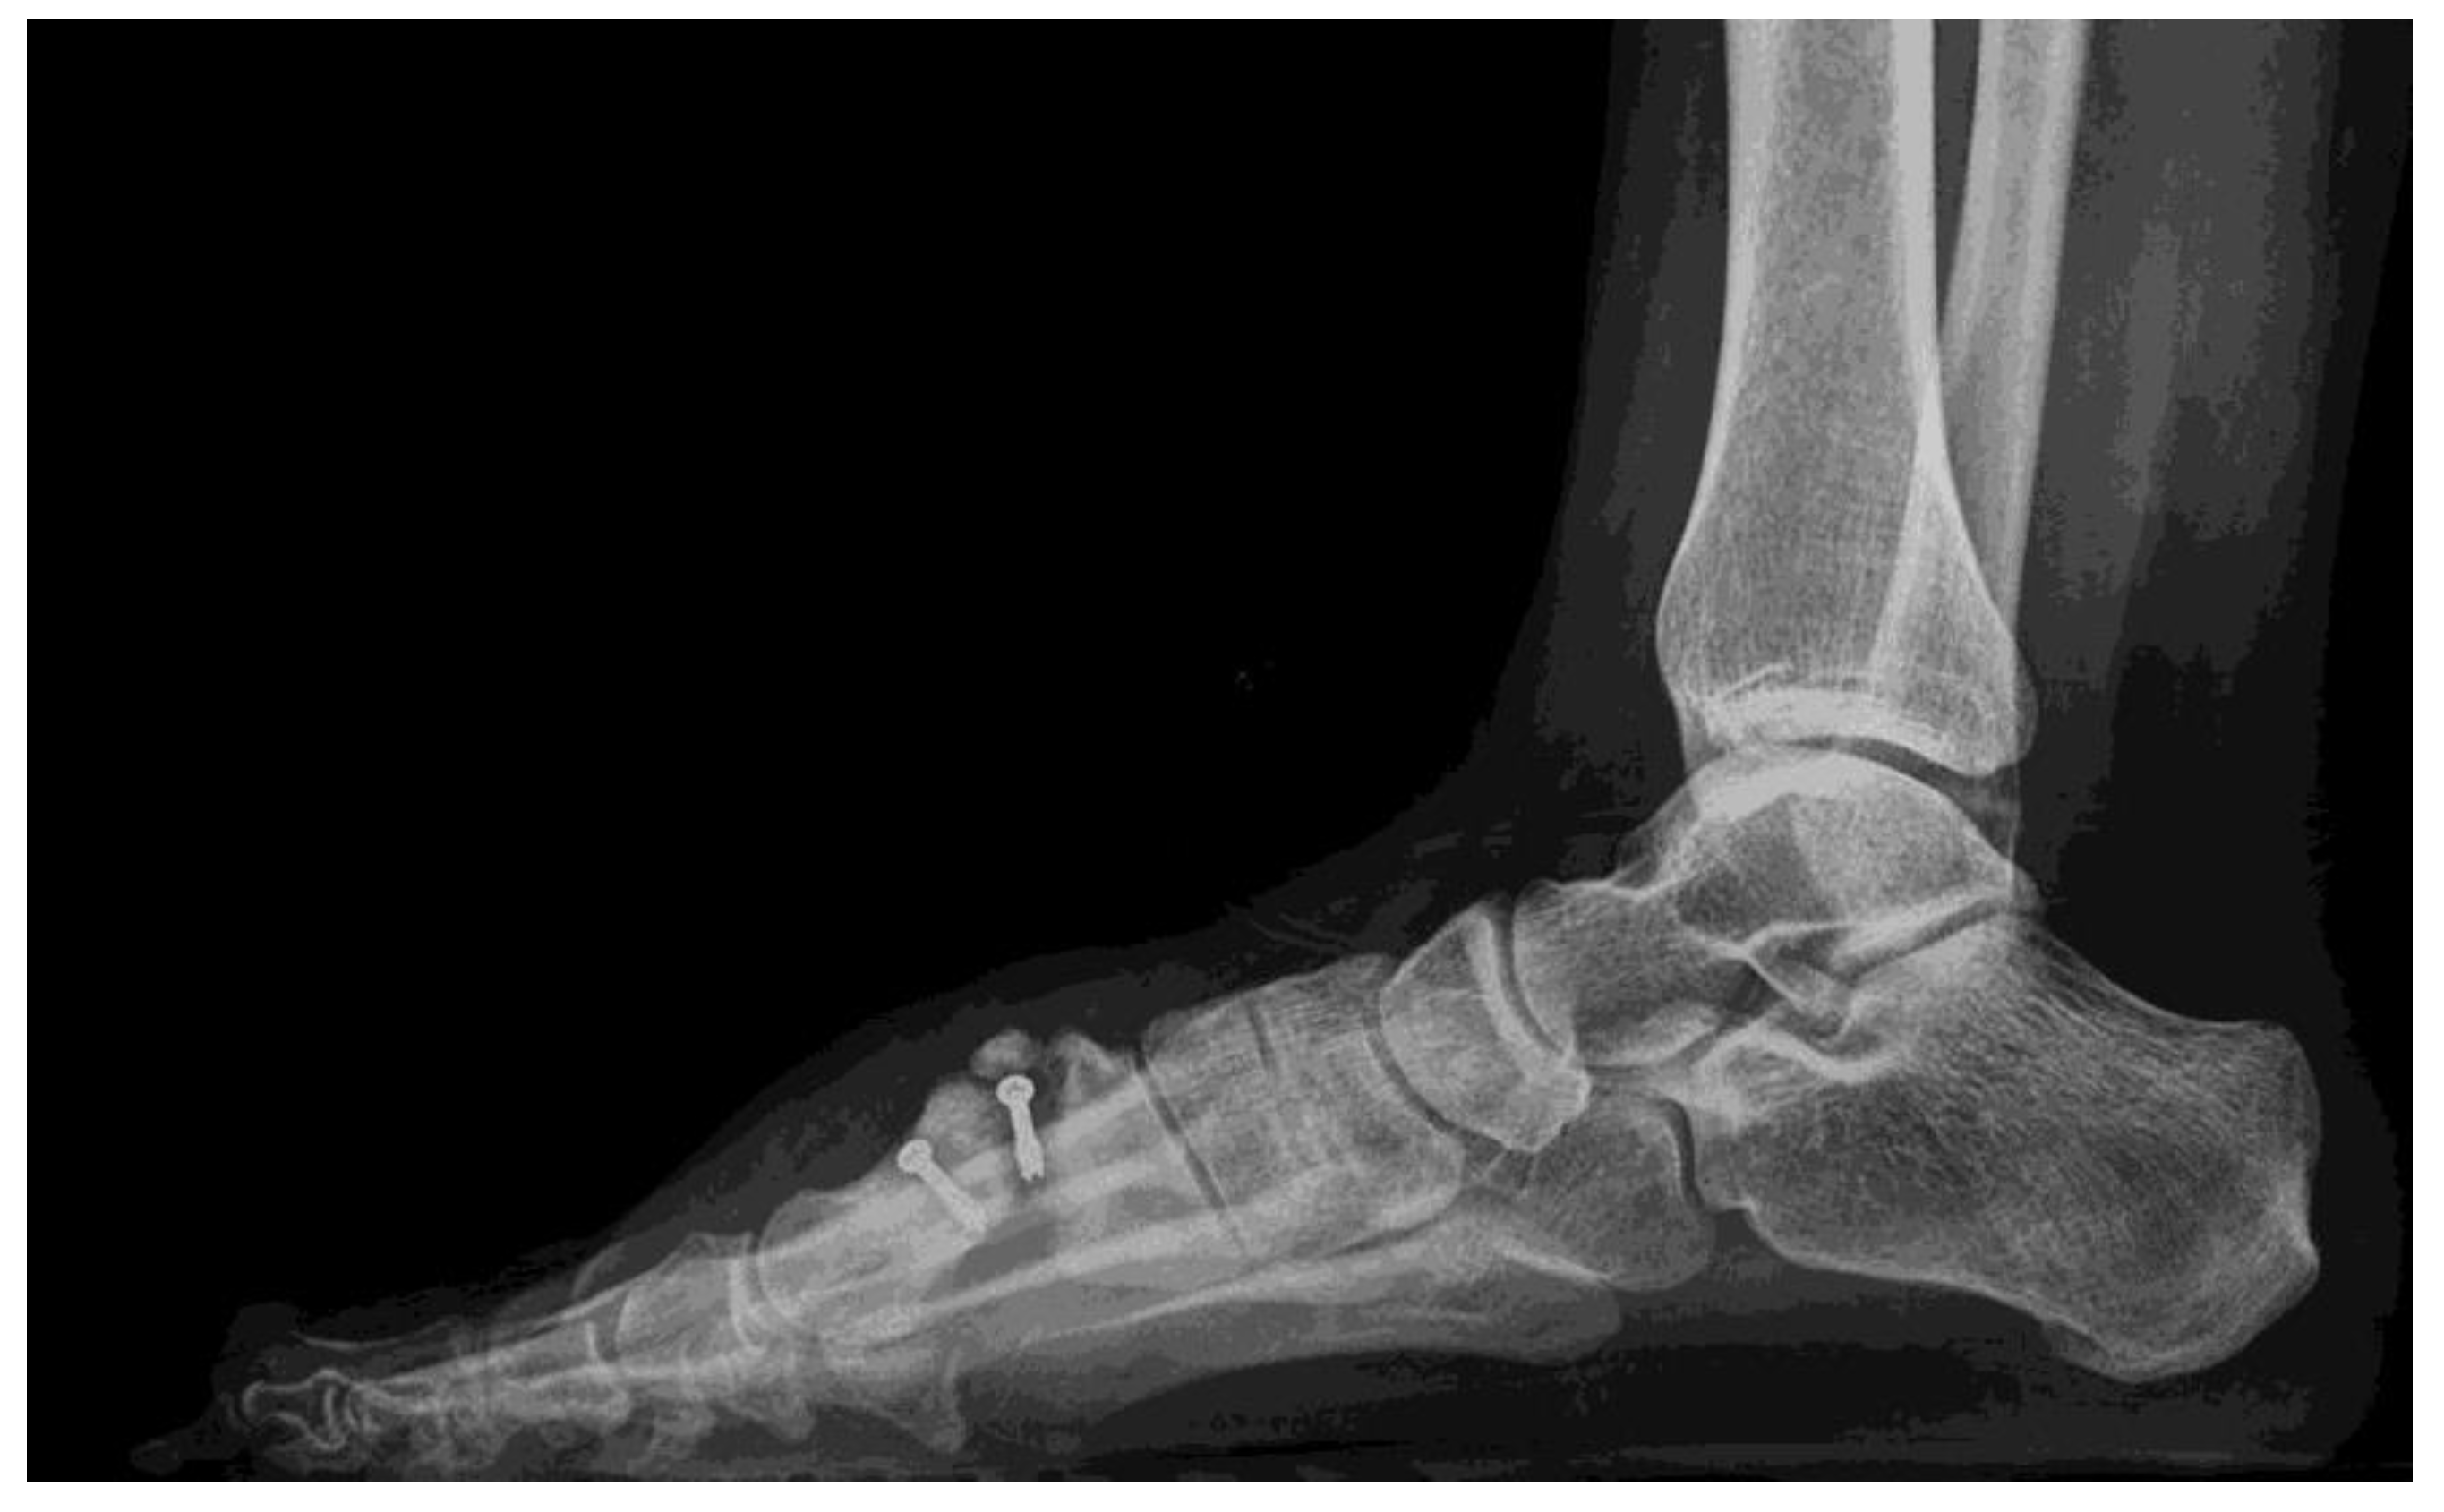

2. Case Report

2.1. Surgical Procedure

2.2. Postsurgical Procedure and Evolution

2.3. Results